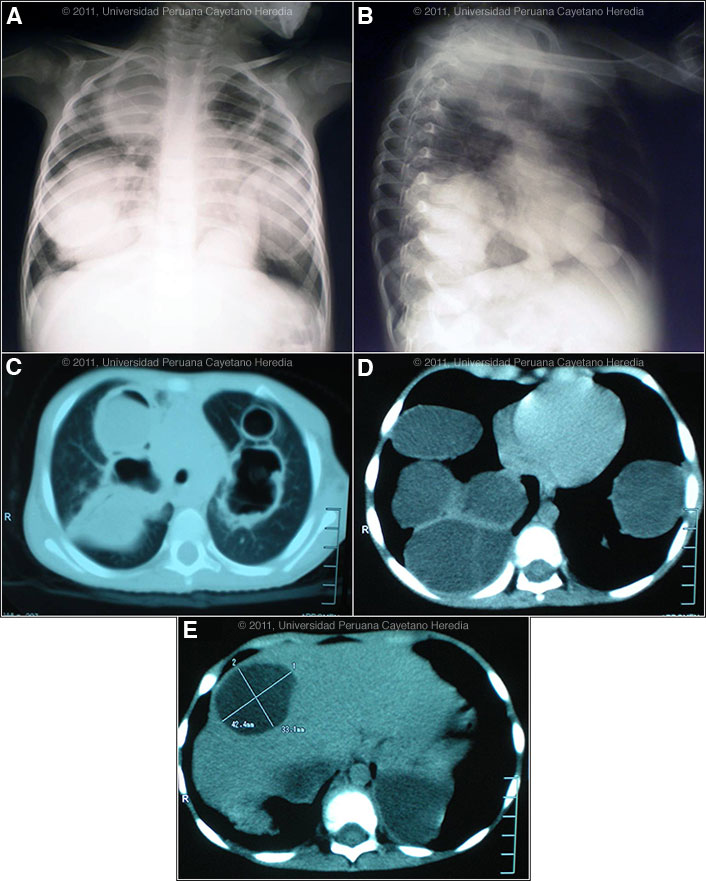

History: Previously healthy, 3-year-old girl admitted with one-year history of epigastric pain, 3kg weight loss in the 3 months prior to admission, and fever, cough and respiratory distress one month before admission. She was diagnosed with pneumonia and treated with antibiotics at a local health centre with no improvement. Epidemiology: Born and lives in a rural agricultural town in the highlands of Cuzco Department; received complete immunizations; previously healthy. Patient helps in tending sheep, cattle, and other farm animals. No specific TB exposures. Physical Examination: Respiratory rate: 60, HR: 130, Temperature: 38.5°C. Acutely ill with moderate respiratory distress. No edema, no cyanosis, HEENT: normal. Lungs: intercostal retractions on normal respiration with no rales. Enlarged liver (4 cm below right margin). No splenomegaly or lymphadenopathy. Chest x-ray and CT scan are shown [Images A-E]. Laboratory: Hct 41. WBC 10,600 (3 band, 52 neutrophils, 6 Eosinophils, 4 monos, 35 lymps). Glucose 101, BUN 17. Creatinine normal.

Diagnosis: Pulmonary and hepatic hydatid cysts due to Echinococcus granulosus.

![]() Discussion: The large cysts on chest x-ray and CT scan are diagnostic of hydatid disease. See previous cases of the week for radiologic presentations in those cases [Gorgas Cases 2010-05, 2008-02, 2001-01, 2005-10]. In this case, the density of the cyst fluid in the chest lesions, some perilesional infiltrate and the fever are highly suggestive of bacterial superinfection of the cysts. This may occur due to a small spontaneous tear in a cyst or via a bronchial fistula (possible fistula here but not clear from the images). In adults the expectoration of salty-tasting fluid is highly characteristic of a fistula or frank rupture of a cyst into a bronchus, but children may not be able to describe this. Western blot for E. granulosus was pending at the time of our visit. Images F & G show a pulmonary hydatid in situ in another patient of ours [Gorgas Case 2008-02]. Serology is usually positive with hepatic cysts but sensitivity drops below 50% with solitary pulmonary cysts even when the cyst is large. With the large burden of disease in this patient’s lung and liver a positive serology would be expected. Human hydatid disease secondary to Echinococcus granulosus is caused by the larval form of this dog tapeworm. Humans ingest the tapeworm eggs in environments contaminated by canine feces and become accidental intermediate hosts. This patient had ongoing exposure to dogs while her parents were working raising cattle and sheep. Sheep are the normal intermediate hosts. In general, disease is diagnosed in adulthood as larval cysts expand slowly over years or decades, becoming symptomatic as they impinge on other structures by virtue of their size. The cysts contain hundreds of viable protoscoleces capable of becoming adult tapeworms upon ingestion by a definitive host such as the dog. The internal germinal membrane lining the cyst produces new protoscoleces on an ongoing basis. Each protoscolex is capable of becoming a new daughter cyst should the original cyst rupture or be ruptured. However it is unusual to see secondary pulmonary cysts from bronchial seeding after a rupture of a cyst into a bronchus, as may have occurred in this case. This is probably due to adhesion of protoscoleces to mucus secretions in the airways and to ciliary movement that will eliminate the protoscoleces subsequent to the cough reflex. Cystic hydatid disease due to E. granulosis is common in sheep and cattle raising areas worldwide. Most primary infections involve a single cyst. In adults, 65% of solitary cysts are found in liver, 25% in lung and the rest in a wide variety of other organs including kidney, spleen, heart, bone and brain. In patients with a pulmonary cyst, approximately 18% will also have a hepatic cyst. Bilateral lung hydatid cysts are present in 6% of adults but in up to 30% of children [Pediatr Radiol. 1978 Sep 26;7(3):164-71]. In our experience in Perú 3.8% of pulmonary cysts are bilateral. A number of series from Europe consider pulmonary involvement to be more common than hepatic in children but a recent series from Latin America found the opposite [Rev Argent Microbiol. 2009 Apr-Jun;41(2):105-11]. In that series, 59% of pediatric cases were male, 28% of pediatric cases were under age 6, and average cyst size was only 2.6 cm. Thus, the extensive disease in this child age 3 is unusual and one can hypothesize infection at a very young age with either (1) a very large inoculum seeding widely, or (2) a subsequent traumatic rupture into a bronchus with wide seeding. Many experienced pediatric clinicians have observed faster than usual growth of lung cysts in young children due to laxer and more permissive parenchymal tissue when compared to adults. The presentation of pulmonary hydatid varies widely, making a uniform treatment recommendation impossible. For single, intact, uncomplicated pulmonary cysts surgery is the treatment of choice, though a trial of albendazole alone may used alone on small (<5 cm), uncomplicated lung cysts. In term of possible drug therapy, praziquantel is the most potent scolicidal drug and is the drug of choice for all adult tapeworms. In hydatid disease, praziquantel is unlike albendazole and does not penetrate the cyst wall or produce measurable concentrations in cyst fluid. Praziquantel is also ineffective against the germinal membrane of cysts, but is able to reliably and quickly kill free protoscoleces [Acta Trop. 2009 Aug;111(2):95-101]. Thus, praziquantel is useful as an acute therapy when a cyst ruptures (spontaneously, or intra-operatively due to surgical mishap) and scoleces are lying free before encysting again. A recent international consensus document [Acta Trop. 2010 Apr;114(1):1-16] recommends routine pre-operative praziquantel/albendazole therapy for liver cysts only but specifically recommends that albendazole should be avoided pre-operatively in larger lung cysts as softening may complicate surgery. There is no data or experience with the theoretically enticing concept of pre-operative praziquantel for lung lesions. In Perú, albendazole is the therapy of choice for intact cysts that are not operable, such as when there are multiple or disseminated cysts. A trial of continuous albendazole may also be considered for solitary cysts that are less than about 5 cm. Response is generally slow. Combined praziquantel and albendazole for medical therapy of liver or lung hydatid has been reported in several small uncontrolled series and experimental protocols examining combination therapy using are underway in several places. Transfer to Lima for further management of her disease was advised but the patient declined. She is being treated with ceftriaxone and clindamycin for the superinfection and we have recommended she receive several months of albendazole to see if there is any response as surgery would be difficult in a complicated case like this with multiple cysts. Ideally, however, the patient should be treated medically on a specialized unit in case of a catastrophic cyst rupture, which would then require urgent surgery. Any surgical intervention at any point should preserve as much lung parenchyma as possible even at the expense of leaving some intact cysts. In the event of general clinical deterioration, radical procedures are often required for extended parenchymal involvement, severe pulmonary suppuration, and complications.